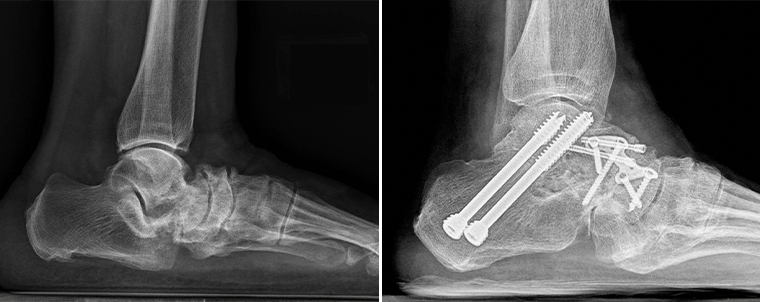

▲患者術前術後的對比圖。(圖/台北慈濟醫院提供)

關於手術的治療方式,王禎麒說明,會將壞死的骨頭移除後,把其他骨頭復位,再取自體髂骨或是以大體老師捐贈的骨頭補在病灶處,加上鋼釘、鋼板讓骨頭更有支撐性,藉由這樣的「關節融合手術」將足踝骨骼融合固定。手術成功率約9成且幾乎不會復發,術後待骨頭品質穩定,須搭配助行器復健,訓練肌力、關節活動度。而相關手術成果也指導骨科年輕醫師發表在2022年的國際知名學術期刊。

王禎麒指出,為了讓影像呈現更加準確,病人需以站立的姿勢進行X光檢查,並輔以電腦斷層評估疾病嚴重等級,經診斷後確認為「穆勒.魏斯氏症」即會依照病程進行治療。初期疼痛較輕微的患者可以透過客製化鞋墊將受力平均分散加上復健治療,避免加劇舟狀骨產生位移,但病程若進展成持續性疼痛、無法以正常步態行走的話就須透過手術治療。